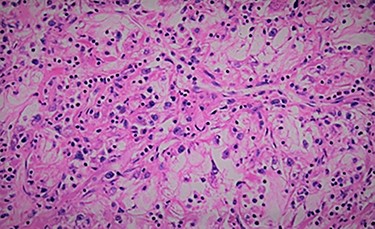

We report the case of 47-year-old men, with a chronic renal failure, who had been operated on 3 years previously for a total left radical nephrectomy for clear cell renal cancer of stage pT3G1N0M0. During the follow-up of the patient, a routine cancer screening with ultrasound revealed a mass in the spleen of about 4 cm of diameter. Laboratory investigations were normal apart from known renal failure (Table 1). Due to known chronic kidney disease and allergy to Iodinated contrast media, an abdominal magnetic resonance imaging (MRI) confirmed the presence of a splenic lesion (Fig. 1). Based on these radiological findings, the splenic mass was diagnosed as a suspicious metastatic lesion. An open splenectomy was performed. The patient recovered uneventfully and was discharged 5 days after surgery. He received pneumococcal, meningococcal and Haemophilus influenzae vaccine. Histologic analysis of the lesion confirmed the presence of clear cell renal cancer metastasis (Fig. 2). The patient was referred to the oncology department for adjuvant treatment with sunitinib. His follow up consisted on abdominal ultrascan (US) every 3 months and MRI at 6 and 12 months from surgery. After 36 months, the patient is doing well with no signs of tumor recurrence.